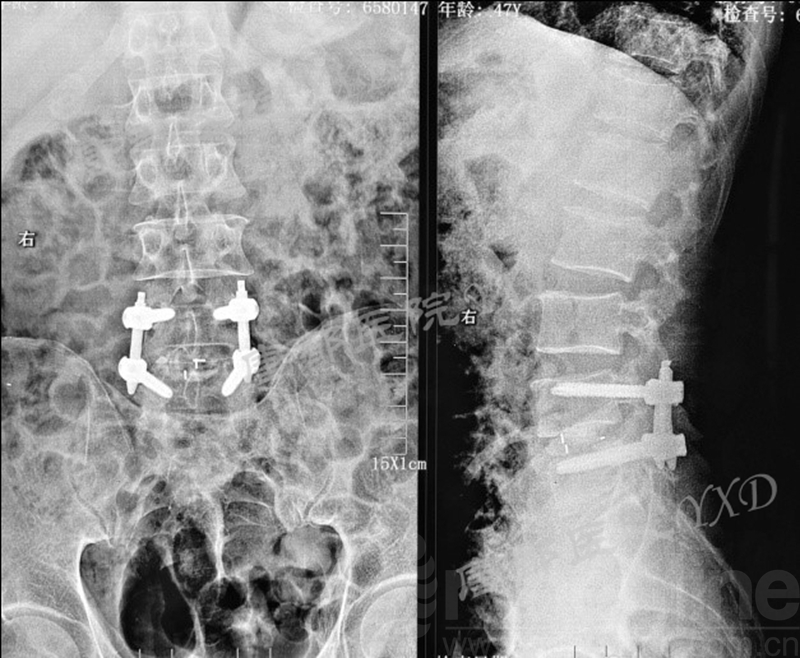

患者47岁,男性。

主诉:腰椎术后左下肢疼痛2月。

专科情况:跛行入病房;左侧直腿抬高试验阳性(60°)、加强试验阳性;左侧足背伸肌力、踇趾背伸肌力3级;左小腿外侧及足背皮肤感觉明显减退;余未见明显异常。VAS评分:左下肢7~8。

既往于半年前因“腰椎间盘突出症(L4-5)”于外院行腰椎侧路脊柱内镜下髓核摘除术(L4-5)。后因症状复发,分别在2周前、10天前于外院行两次腰椎后路脊柱内镜下髓核摘除术(L4-5)。

影像学检查:

诊断:腰椎间盘突出症术后复发

手术方案:显微镜辅助MI-TLIF腰椎翻修术